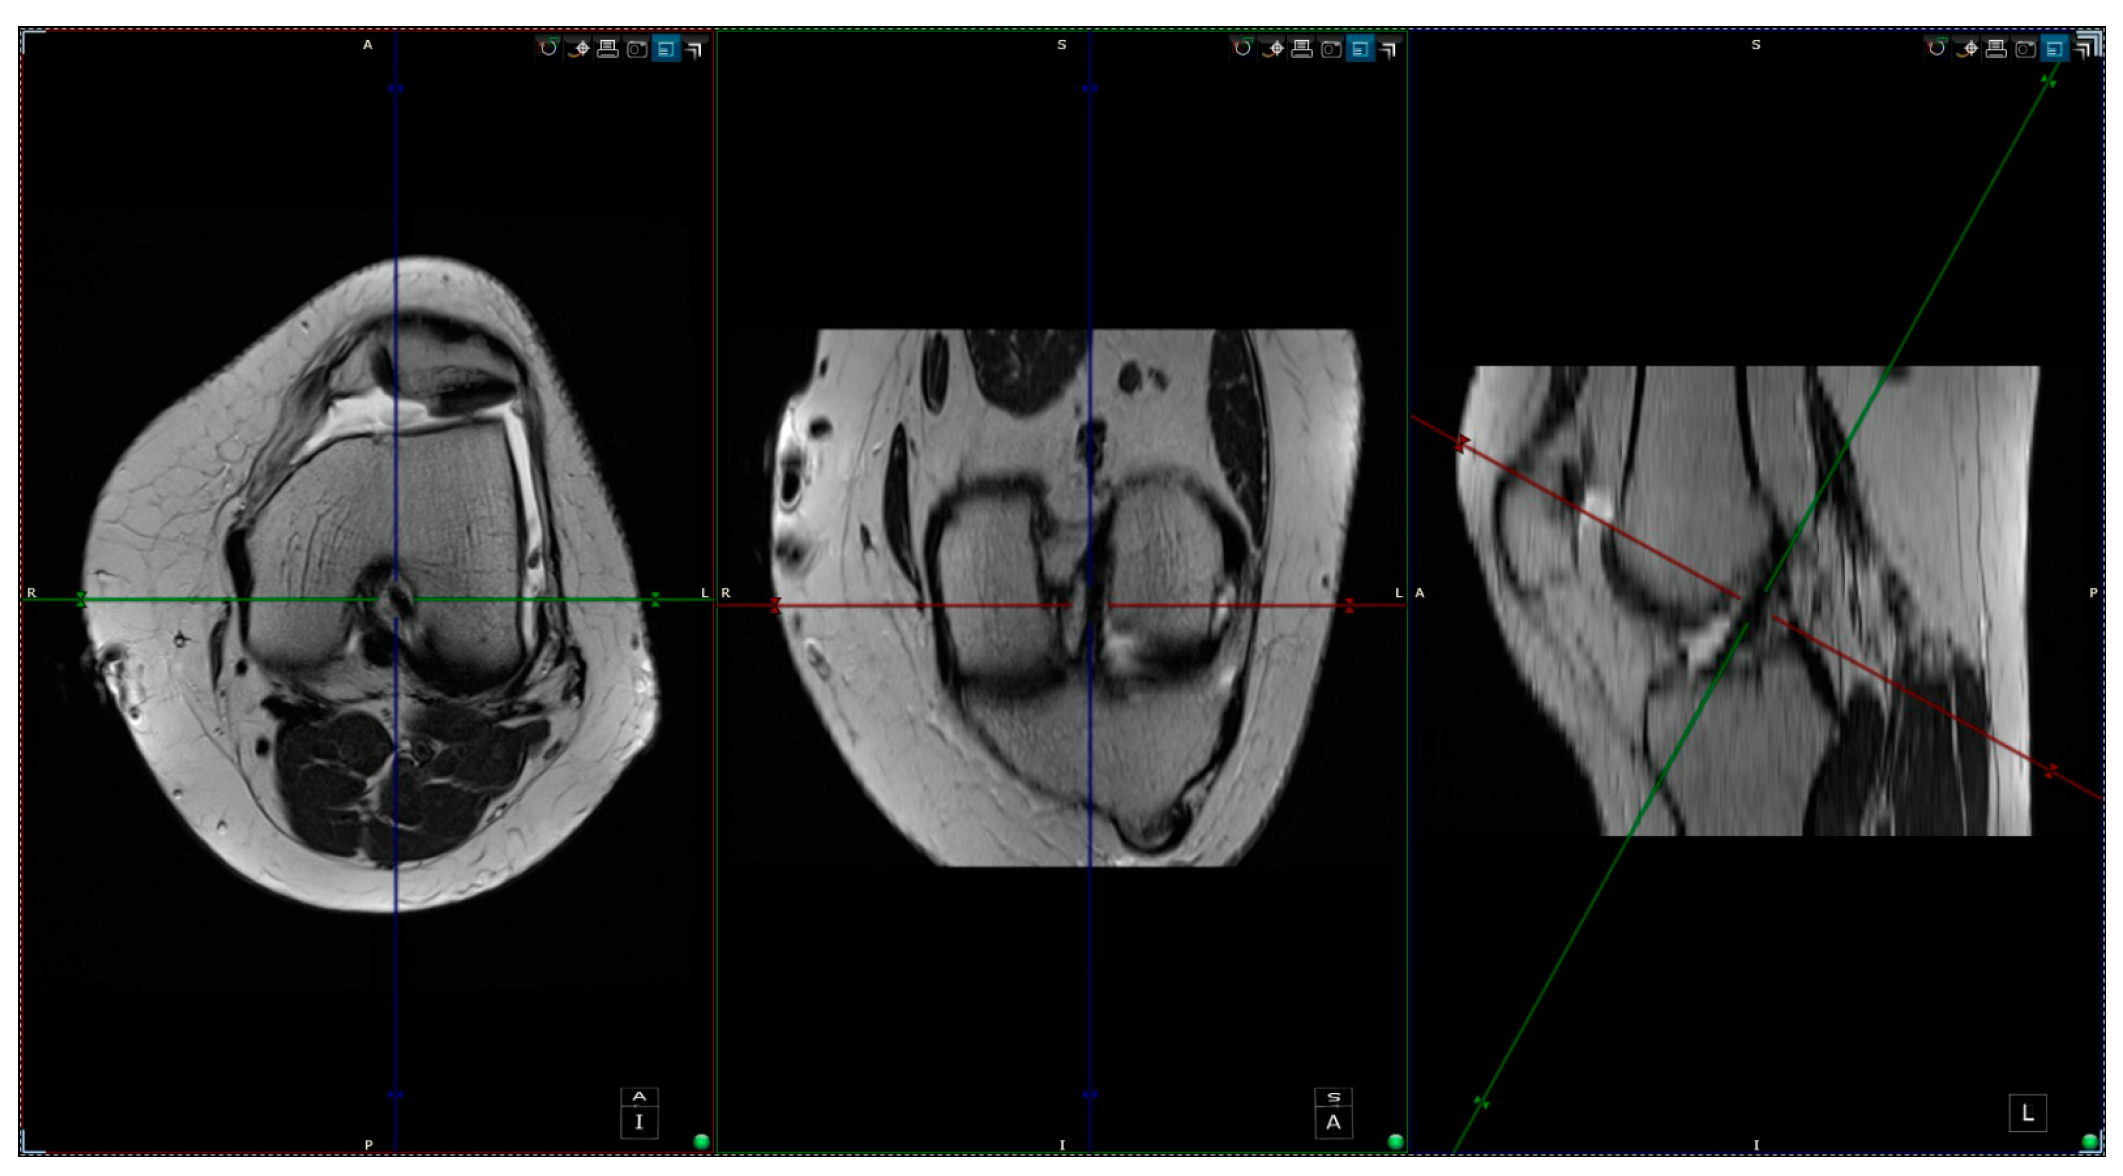

- aICN area: area of the circle defined by three cortical walls of the antero-superior notch (in the custom axial plane/CAP; Figure 3).

- ACL area: area of the closed polygon defined by pointed dots around the cross-section of the anterior cruciate ligament (in the CAP; Figure 4).

- aICN area and ACL area (both appear in Figure 6).